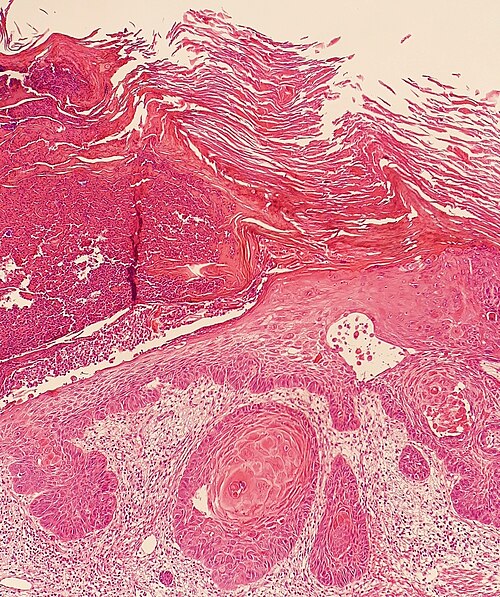

📷 תמונה קלינית

Necrotizing Fasciitis

Necrotizing Fasciitis: אריתמה מפושטת עם שינוי צבע לסגלגל-אפור ובולות המורגיות בשוק שמאל. זיהום חמור ומהיר-התקדם של הפאשיה והרקמה התת-עורית. מצב חירום כירורגי!

Credit: Smuszkiewicz, Trojanowska, Tomczak | CC BY 2.0 | Wikimedia Commons